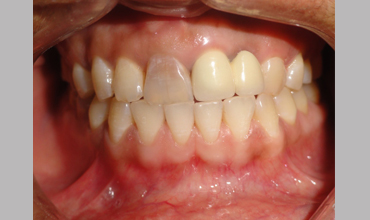

Management Of Internal Root Resorption In Maxillary Central Incisor Pre-operative Radiograph Removal Of Granulation Tissue With Ultra

Management Of Internal Root Resorption In Maxillary Central Incisor